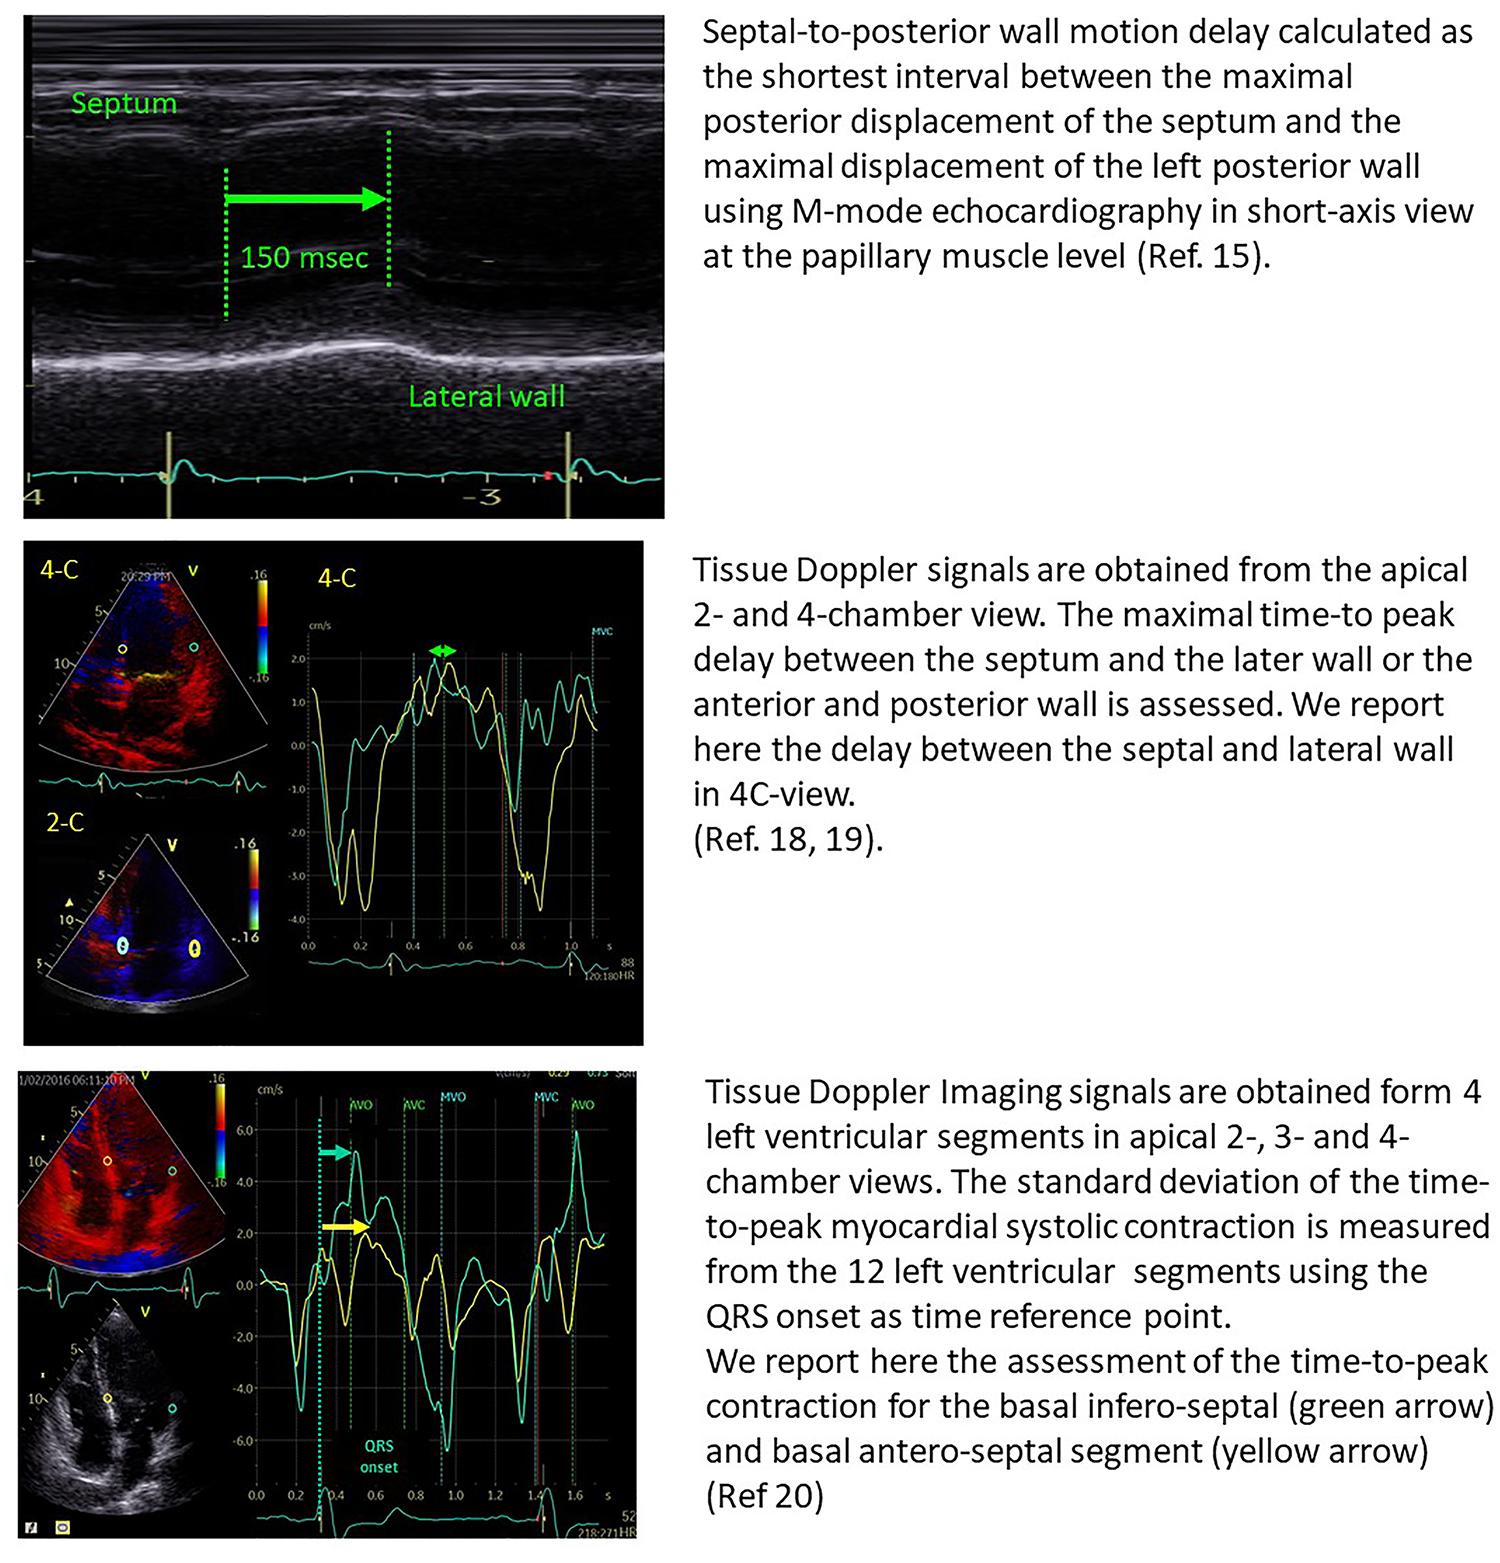

The initial imaging studies on LV mechanical dyssynchrony were focused on the measure of opposite wall delay by different echocardiographic modalities.

In 24 patients with heart failure, Pitzalis et al. showed that a septal-to-posterior motion delay ≥130 msec was able to predict LV reverse remodelling, with a positive predictive value of 80% and an accuracy of 85% (15). However, this approach was not suitable for patients with previous anterior or septal infarction and was plagued by poor temporal resolution (16). Successive studies, therefore, focused on tissue Doppler imaging and speckle tracking echocardiography for the assessment of LV dyssynchrony, by the estimation of opposite wall delay (17), or by focusing on the difference in peak systolic velocities of different myocardial regions (18–20) (Figure 1). Despite all these studies being able to show the good performance of echo-derived parameters for the prediction of CRT response in small, retrospective cohorts, the multicentric PROSPECT trial did not confirm the applicability of echocardiographic measures of dyssynchrony for the selection of CRT candidates (2).

Figure 1

Examples of the estimation of opposite wall delay in CRT candidates according to the main methods described in the literature. Upper panel: Pitzalis’ method; Middle panel: Bax's method; Lower panel: Yu's method.